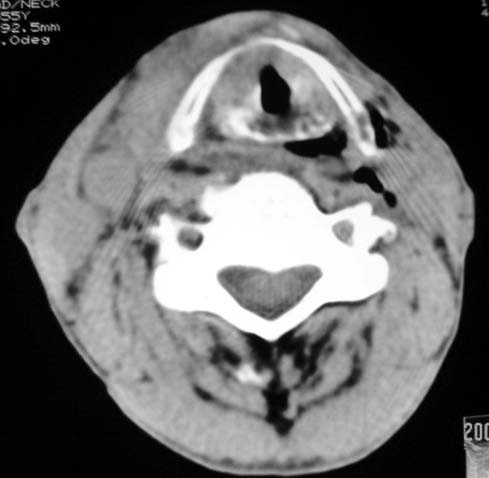

以下是引用dyqct在2007-4-20 16:19:00的发言:[br]考虑:1、左侧梨状窝区破裂伴左颈深、浅部气肿。[br] 2、右侧甲状腺区血肿(请追问病史是否伤及右颈部)。[br] 3、建议病情稳定后增强扫描除外右侧甲状腺腺瘤。